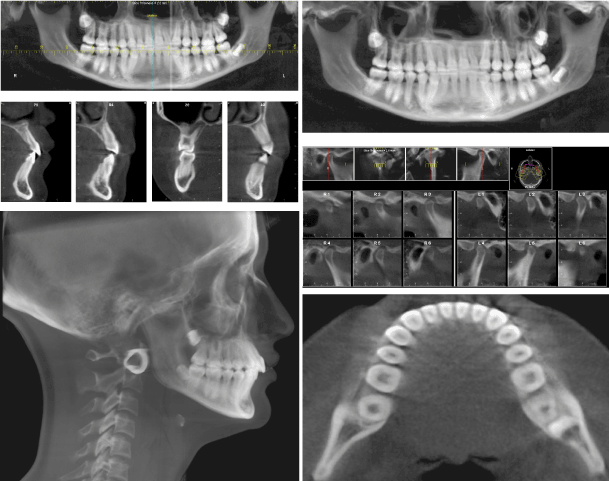

Figure 3. LATERAL CRANIUM RX

Normal facial height – second class skeletal pattern due to retrusive mandible – upper and lower incisors proclined – forward mandibular growing direction, changes toward clockwise rotation, due to upper and lower incisors contact – 3mm overjet - 2mm overbite.

Frontal RX: Inclined occlusal plane – mandibular right deviation (Figure 4)

Palatal suture: Open suture (Figure 5)

Temporo mandibular joint: Retropositioned, curved and flattened condyles (Figure 6)

After a year, photos in static and dinamic position, extraoral photos and CBCT images (Figures 16-19) and Table 2

Figure 18. FINAL CBCT IMAGES

Figure 19. SUPERIMPOSITION (Na-Ba at CC) and PROFILE

-Mandibular movements 2021 Copyright OAT. All rights reserv>

-Good face profile and teeth exposure during smile

-Good position of root between cortical alveolar bone (see cross sections)

-The root and palatal face of crown of tooth 2.2, are not regular

-Initial and final cefalometric values are not chenged so much. The mandible has moved forward and upper incisors inclination is increased

-Each condyle is placed in the center of its fossa

-Dental arch has a regular and wide form

-Wisdom teeth should be extracted